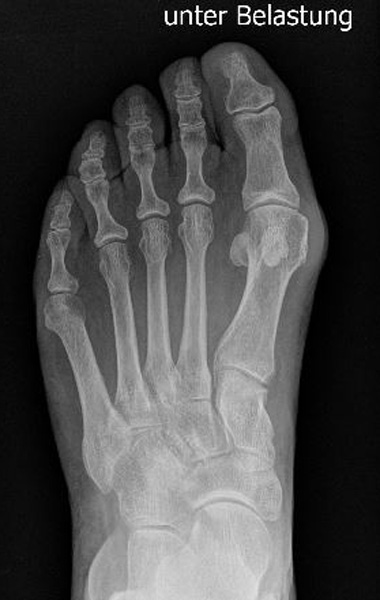

Abb. 12a: Typ III Deformität präoperativ im belasteten dp Röntgenbild.